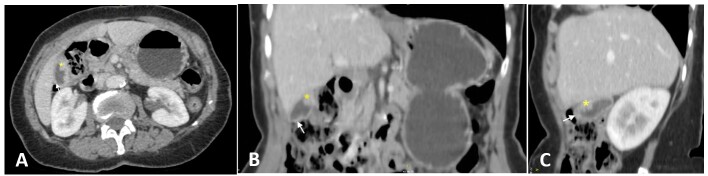

Schistosomiasis is an infectious disease caused by parasitic flatworms of the genus Schistosoma. The species Schistosoma mansoni is associated with hepatosplenic disease. Schistosomiasis involving the gallbladder alone is highly unusual, with a few cases reported. Herein, we present the case of a woman from a region with endemic schistosomiasis who presented with a painless solid lesion and wall thickening of the gallbladder. She underwent an uneventful laparoscopic cholecystectomy. Microscopic examination of the surgical specimen revealed Schistosoma mansoni eggs associated with granulomatous reaction, leading to the diagnosis of schistosomiasis of the gallbladder, prompting subsequent treatment with praziquantel and follow-up. This case illustrates the importance of suspicion for this diagnosis in endemic areas, as it can be misdiagnosed with malignancy if not examined microscopically. Complications and treatment strategies are poorly characterized for the few cases of schistosomiasis; reporting this case can serve as a helpful reminder of a rare presentation of this disease.